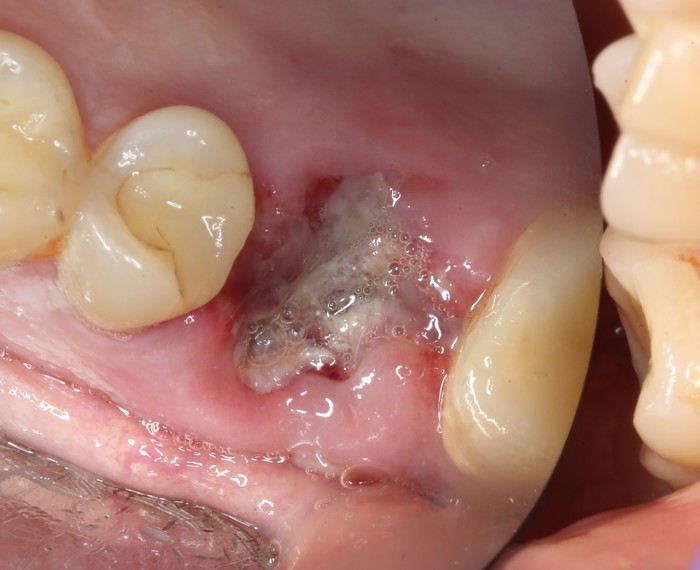

На момент моего осмотра это выглядело так:

Согласитесь, не особо эстетично. Ортопантомограмма: